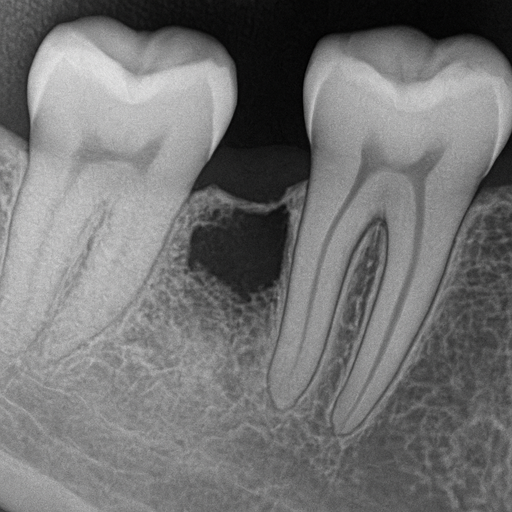

Progres choroby zębów – od próchnicy do ekstrakcji

Progres choroby zębów – od próchnicy do ekstrakcji Czym jest progres choroby zębów Progres choroby zębów to stopniowe pogarszanie się...